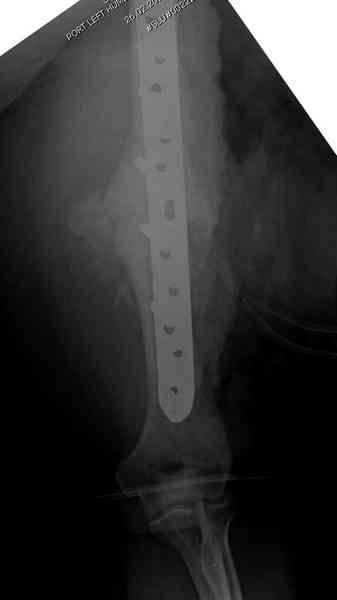

А для стимулирования мы применили массу из состава: OP1 с

деминерализованной костью, добавив к ним еще красную часть,

приготовленную из крови больной. Взятая перед операцией кровь в

количестве 80 мл провели через центрифугу и без сывороточной части

красную матрицу добавили к остальным.

С такой массой наверное ложный сустав "over killed", но надеюсь,

что-то из них при такой фиксации окажет стимулирующее действие.